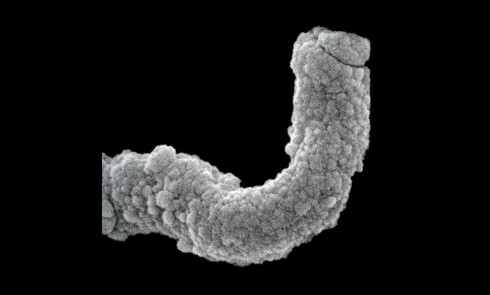

Article réservé à nos abonnés Treponema denticola

Résumé Treponema denticola est une bactérie anaérobie du microbiote buccal symbiotique, impliquée dans la parodontite. Elle est capable d’envahir les tissus...